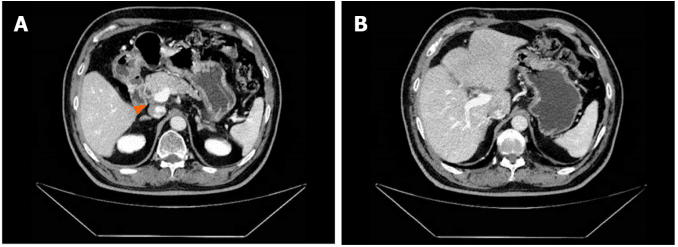

GC-D 方案治疗 6 个月后,肿瘤标志物水平保持相对较低。MCCT 显示肝十二指肠系膜淋巴结数量显著减少,肝 S4 段低密度病灶消失(图 3)。疗效评估为部分缓解(PR)。尽管患者在化疗后两天出现恶心和疲劳加重,但由于治疗效果良好,患者继续接受初始治疗方案。

图 3. GC-D 方案治疗 6 个周期后 MCCT 检查结果

(A:肝十二指肠系膜淋巴结明显缩小;B:低密度灶消失)